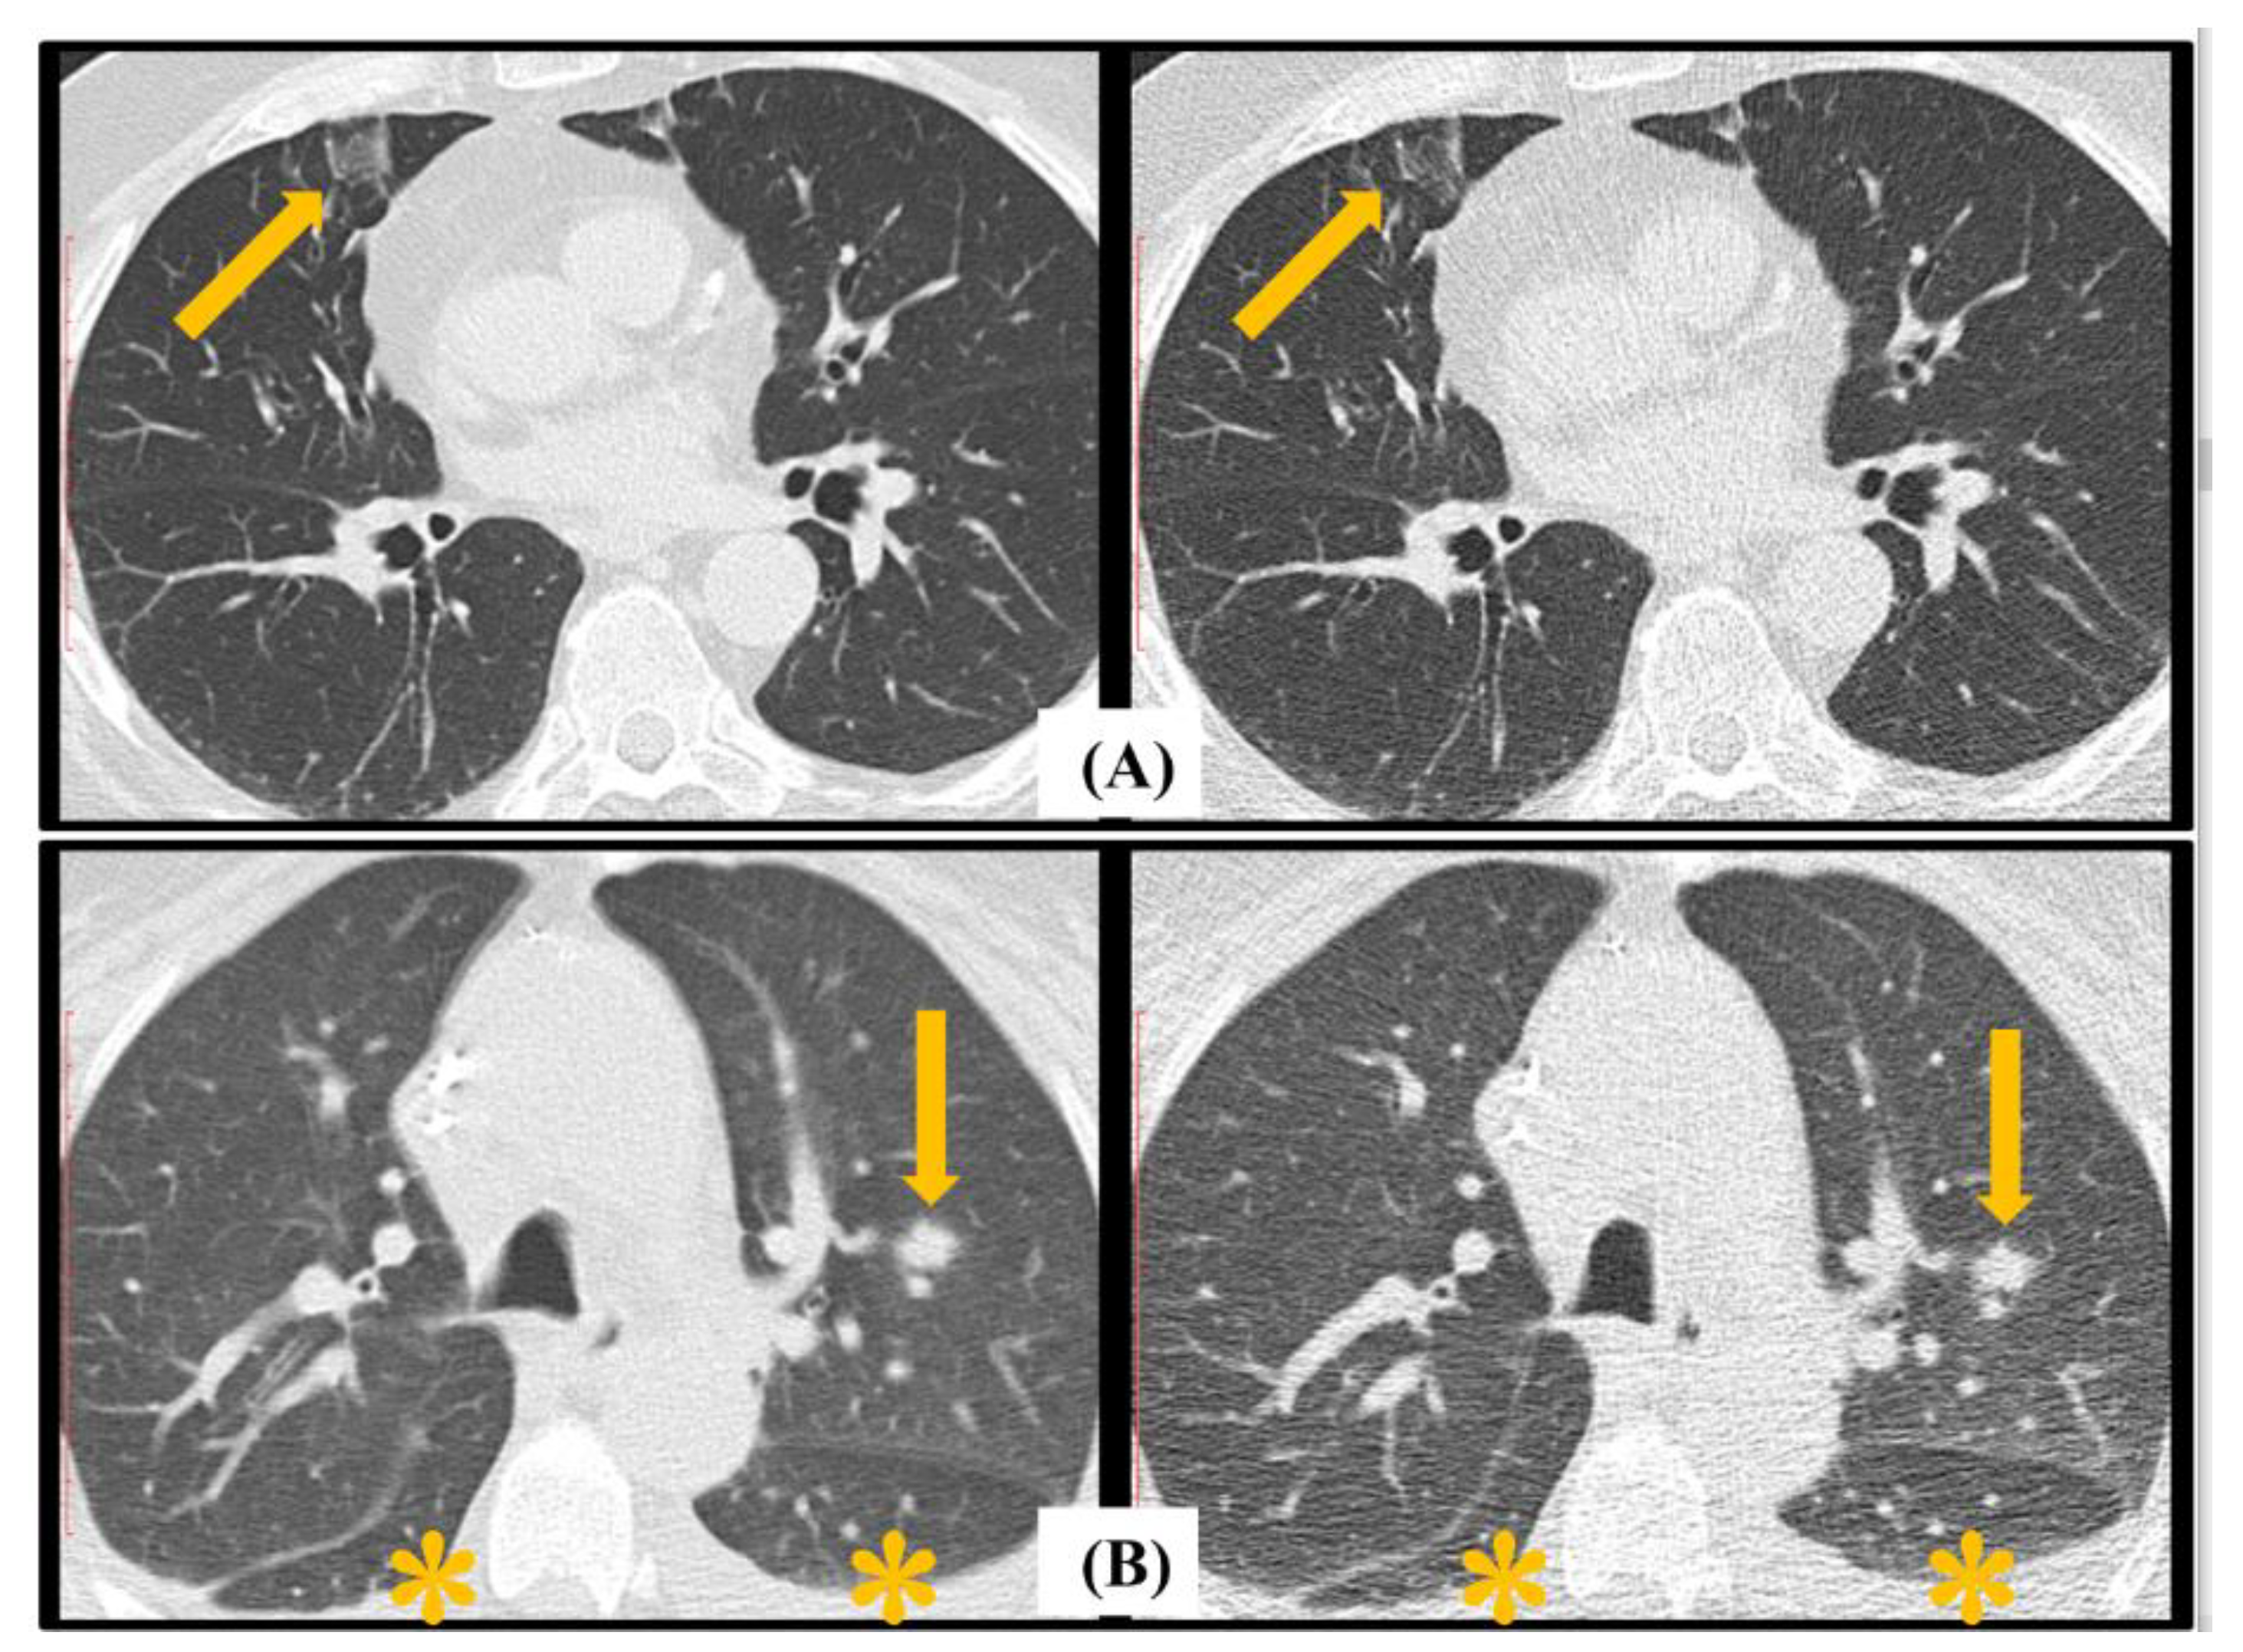

4.3. EORTC Radiological Findings Assessment

5. Discussion